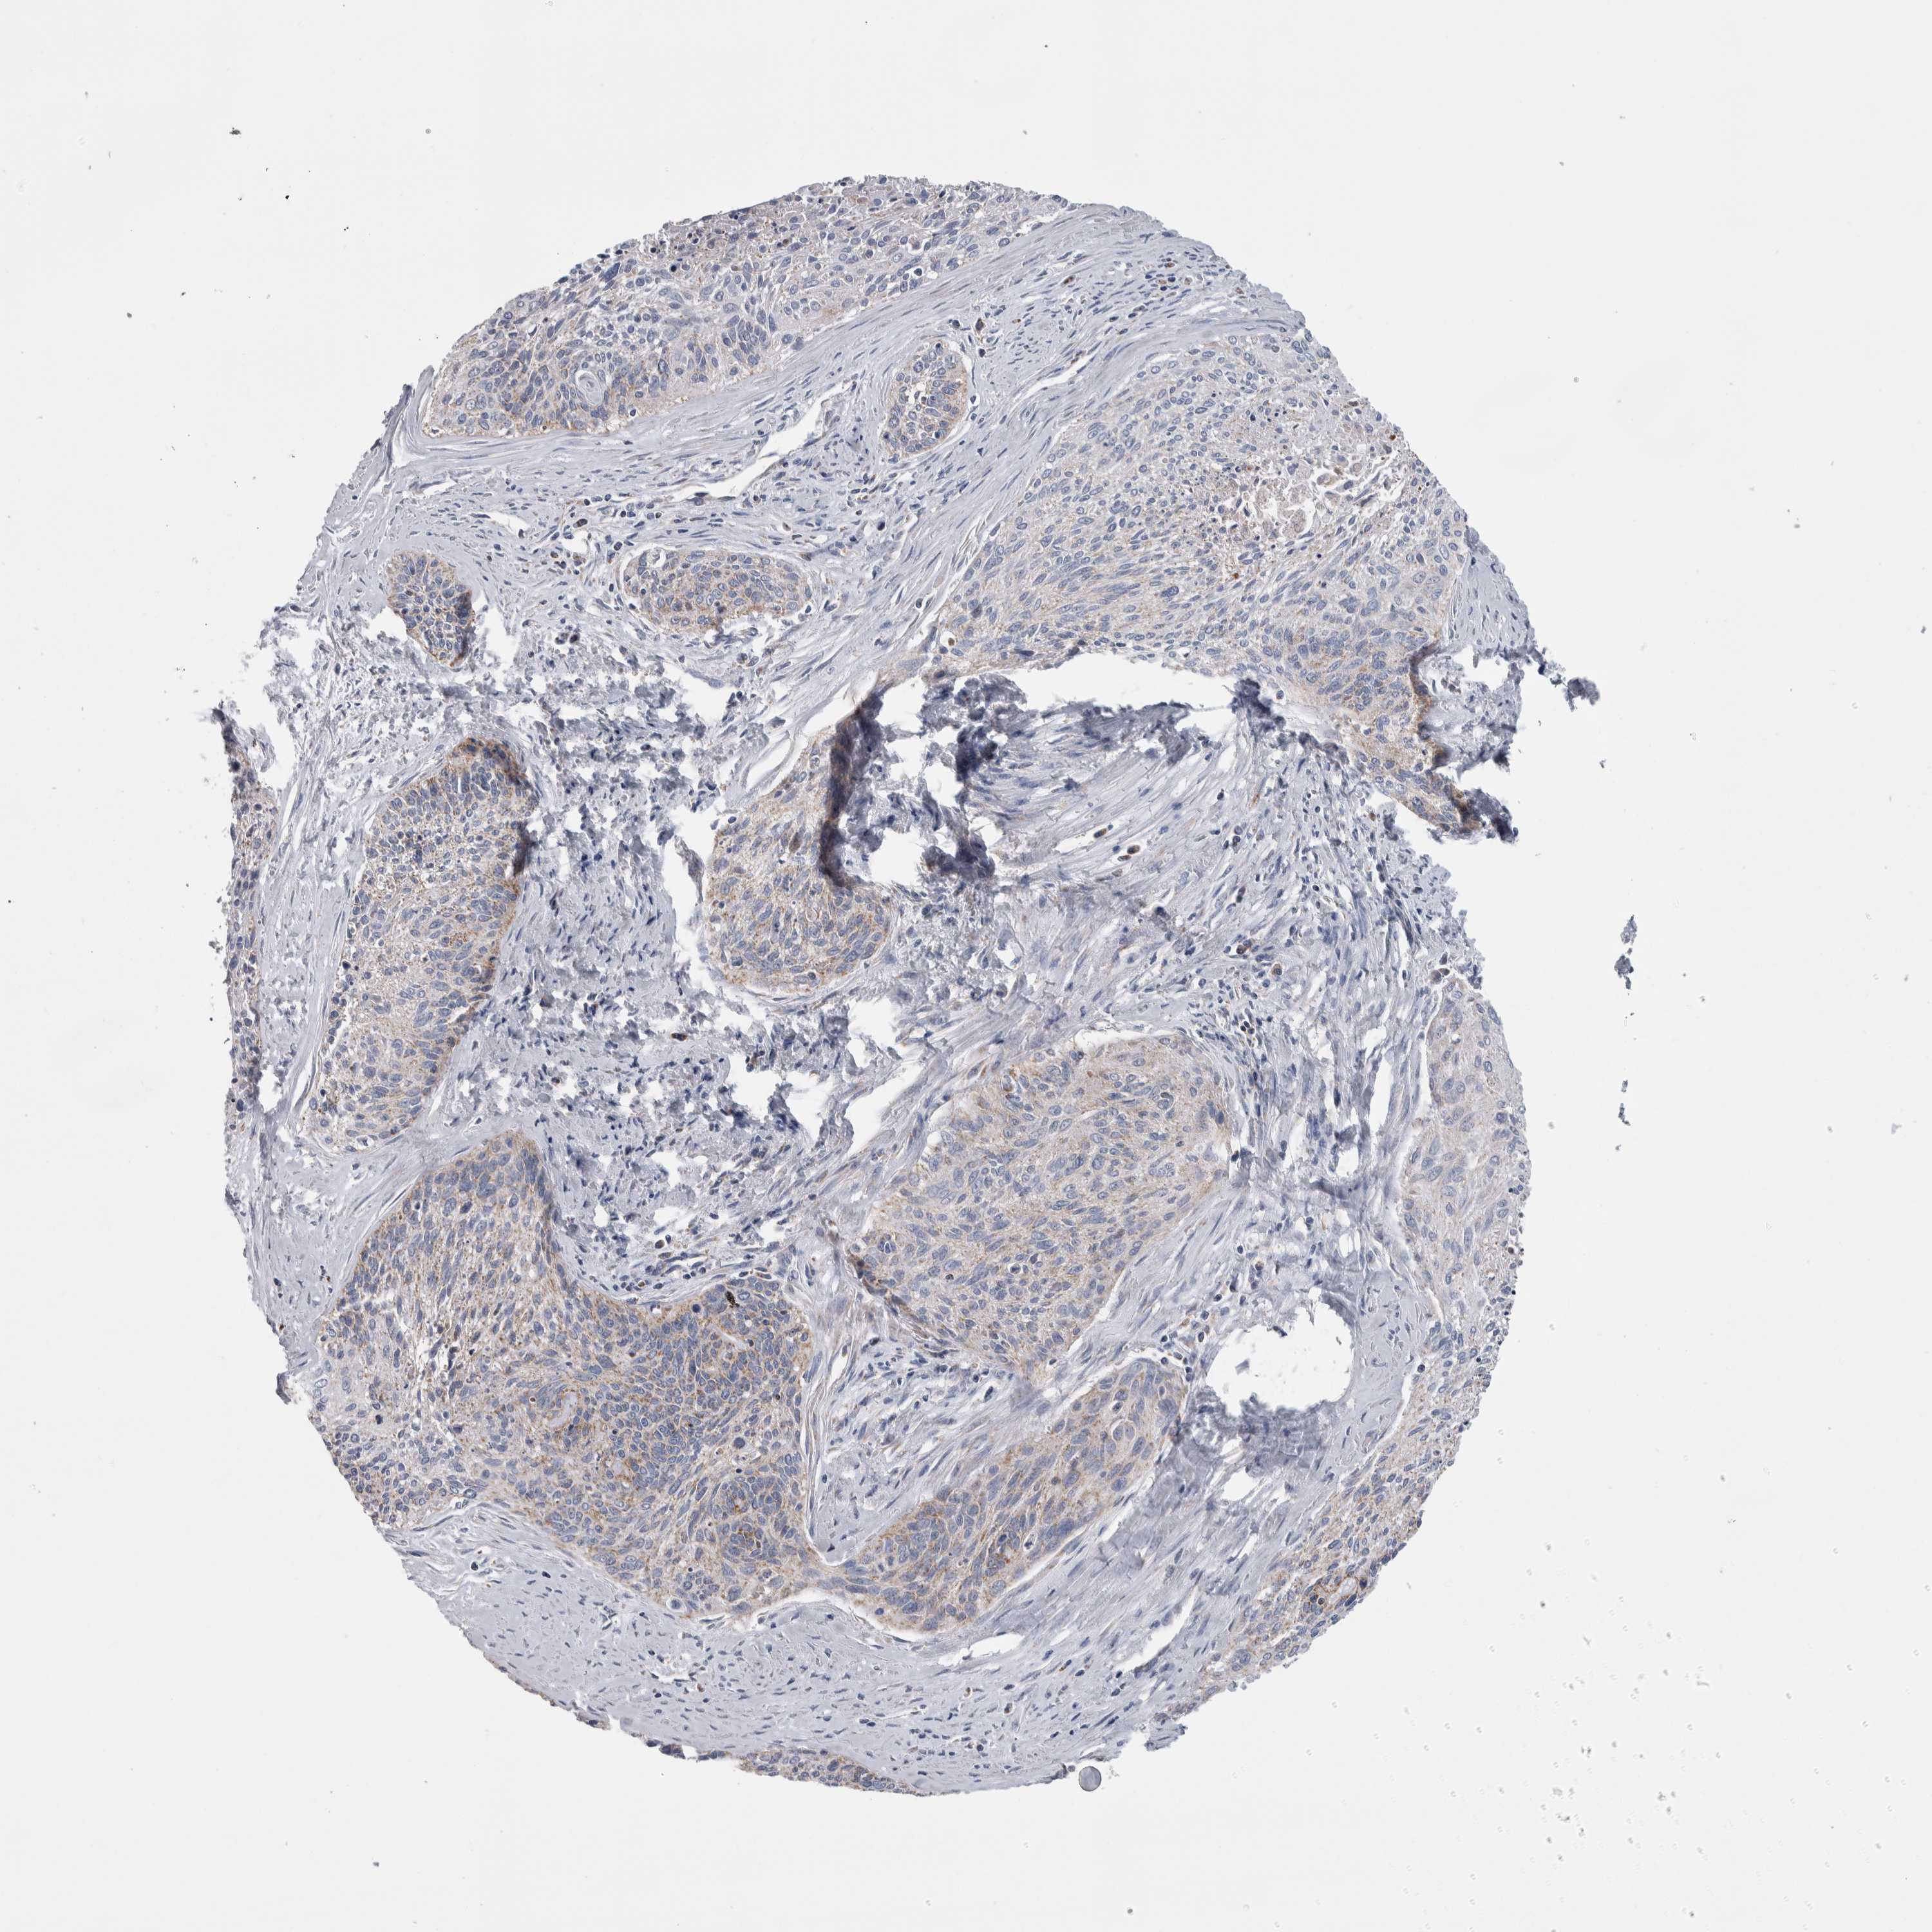

CERVICAL CANCER - Protein expressioni

A mouse-over function shows sample information and annotation data. Click on an image to view it in a full screen mode. Samples can be filtered based on level of antibody staining by selecting one or several of the following categories: high, medium, low and not detected. The assay and annotation is described here.

Note that samples used for immunohistochemistry by the Human Protein Atlas do not correspond to samples in the TCGA dataset.

Antibody stainingi

Antibody staining in the annotated cell types in the current human tissue is reported as not detected, low, medium, or high, based on conventional immunohistochemistry profiling in selected tissues. This score is based on the combination of the staining intensity and fraction of stained cells.

Each image is clickable and will lead to virtual microscopy that enables deeper exploration of all samples and also displays staining intensity scores, fraction scores and subcellular localization as well as patient and tissue information for each sample.

Antibody HPA018990

Antibody HPA018993

Antibody HPA018996

Antibody HPA024089

Squamous cell carcinoma, NOS

Adenocarcinoma, NOS